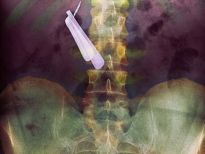

Bu röntgenler gerçek!

Bu röntgenler gerçek! galerisi resim 1

İki çatalı, bir tükenmez kalemi ve diş fırçasını yutmuş bir hasta.